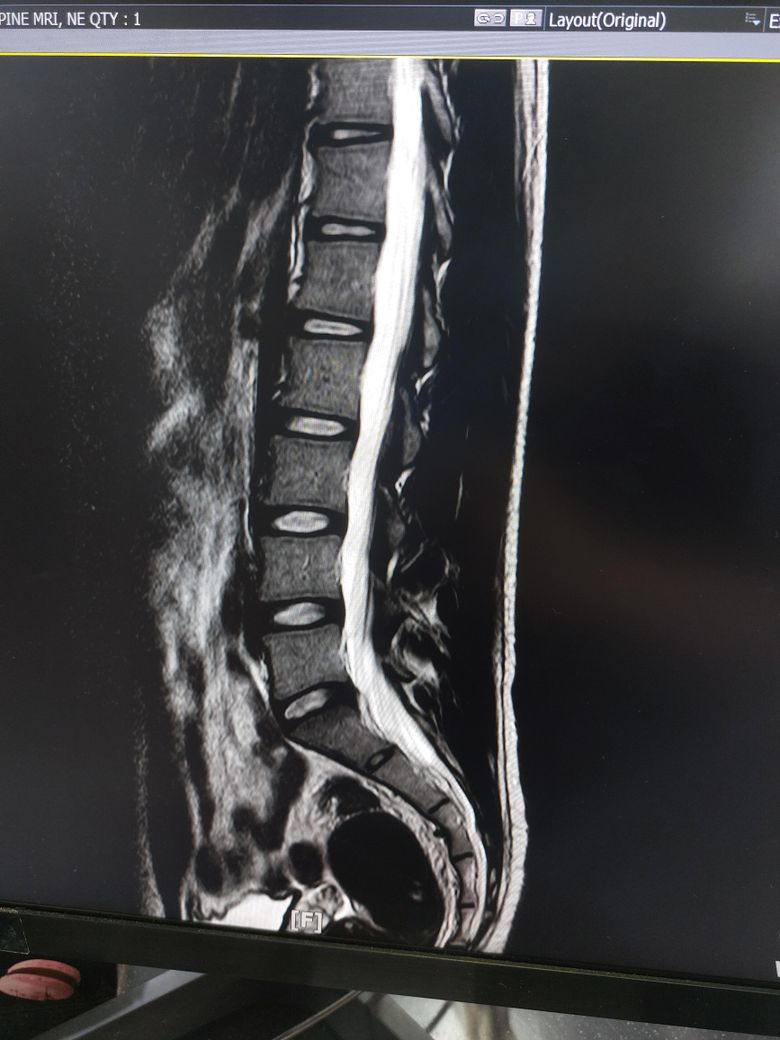

허리디스크 심한편인가요? [Mri 사진 첨부]

멸개월전부터 요추가 뻣뻣하고 시큰거리다가 최근에 좀 나아지긴 해도 만성적이라서 오늘 mri 찍고 허리디스크 진단받았습니다

(요추 맨 밑 천추 위 디스크)

1. 이정도면 아직 팽윤단계인가요?

1. 이정도면 아직 팽윤단계인가요? 디스크 자체도 심하지 않을 뿐더러 그에 따른 증상인지 여부도 확실하지 않습니다